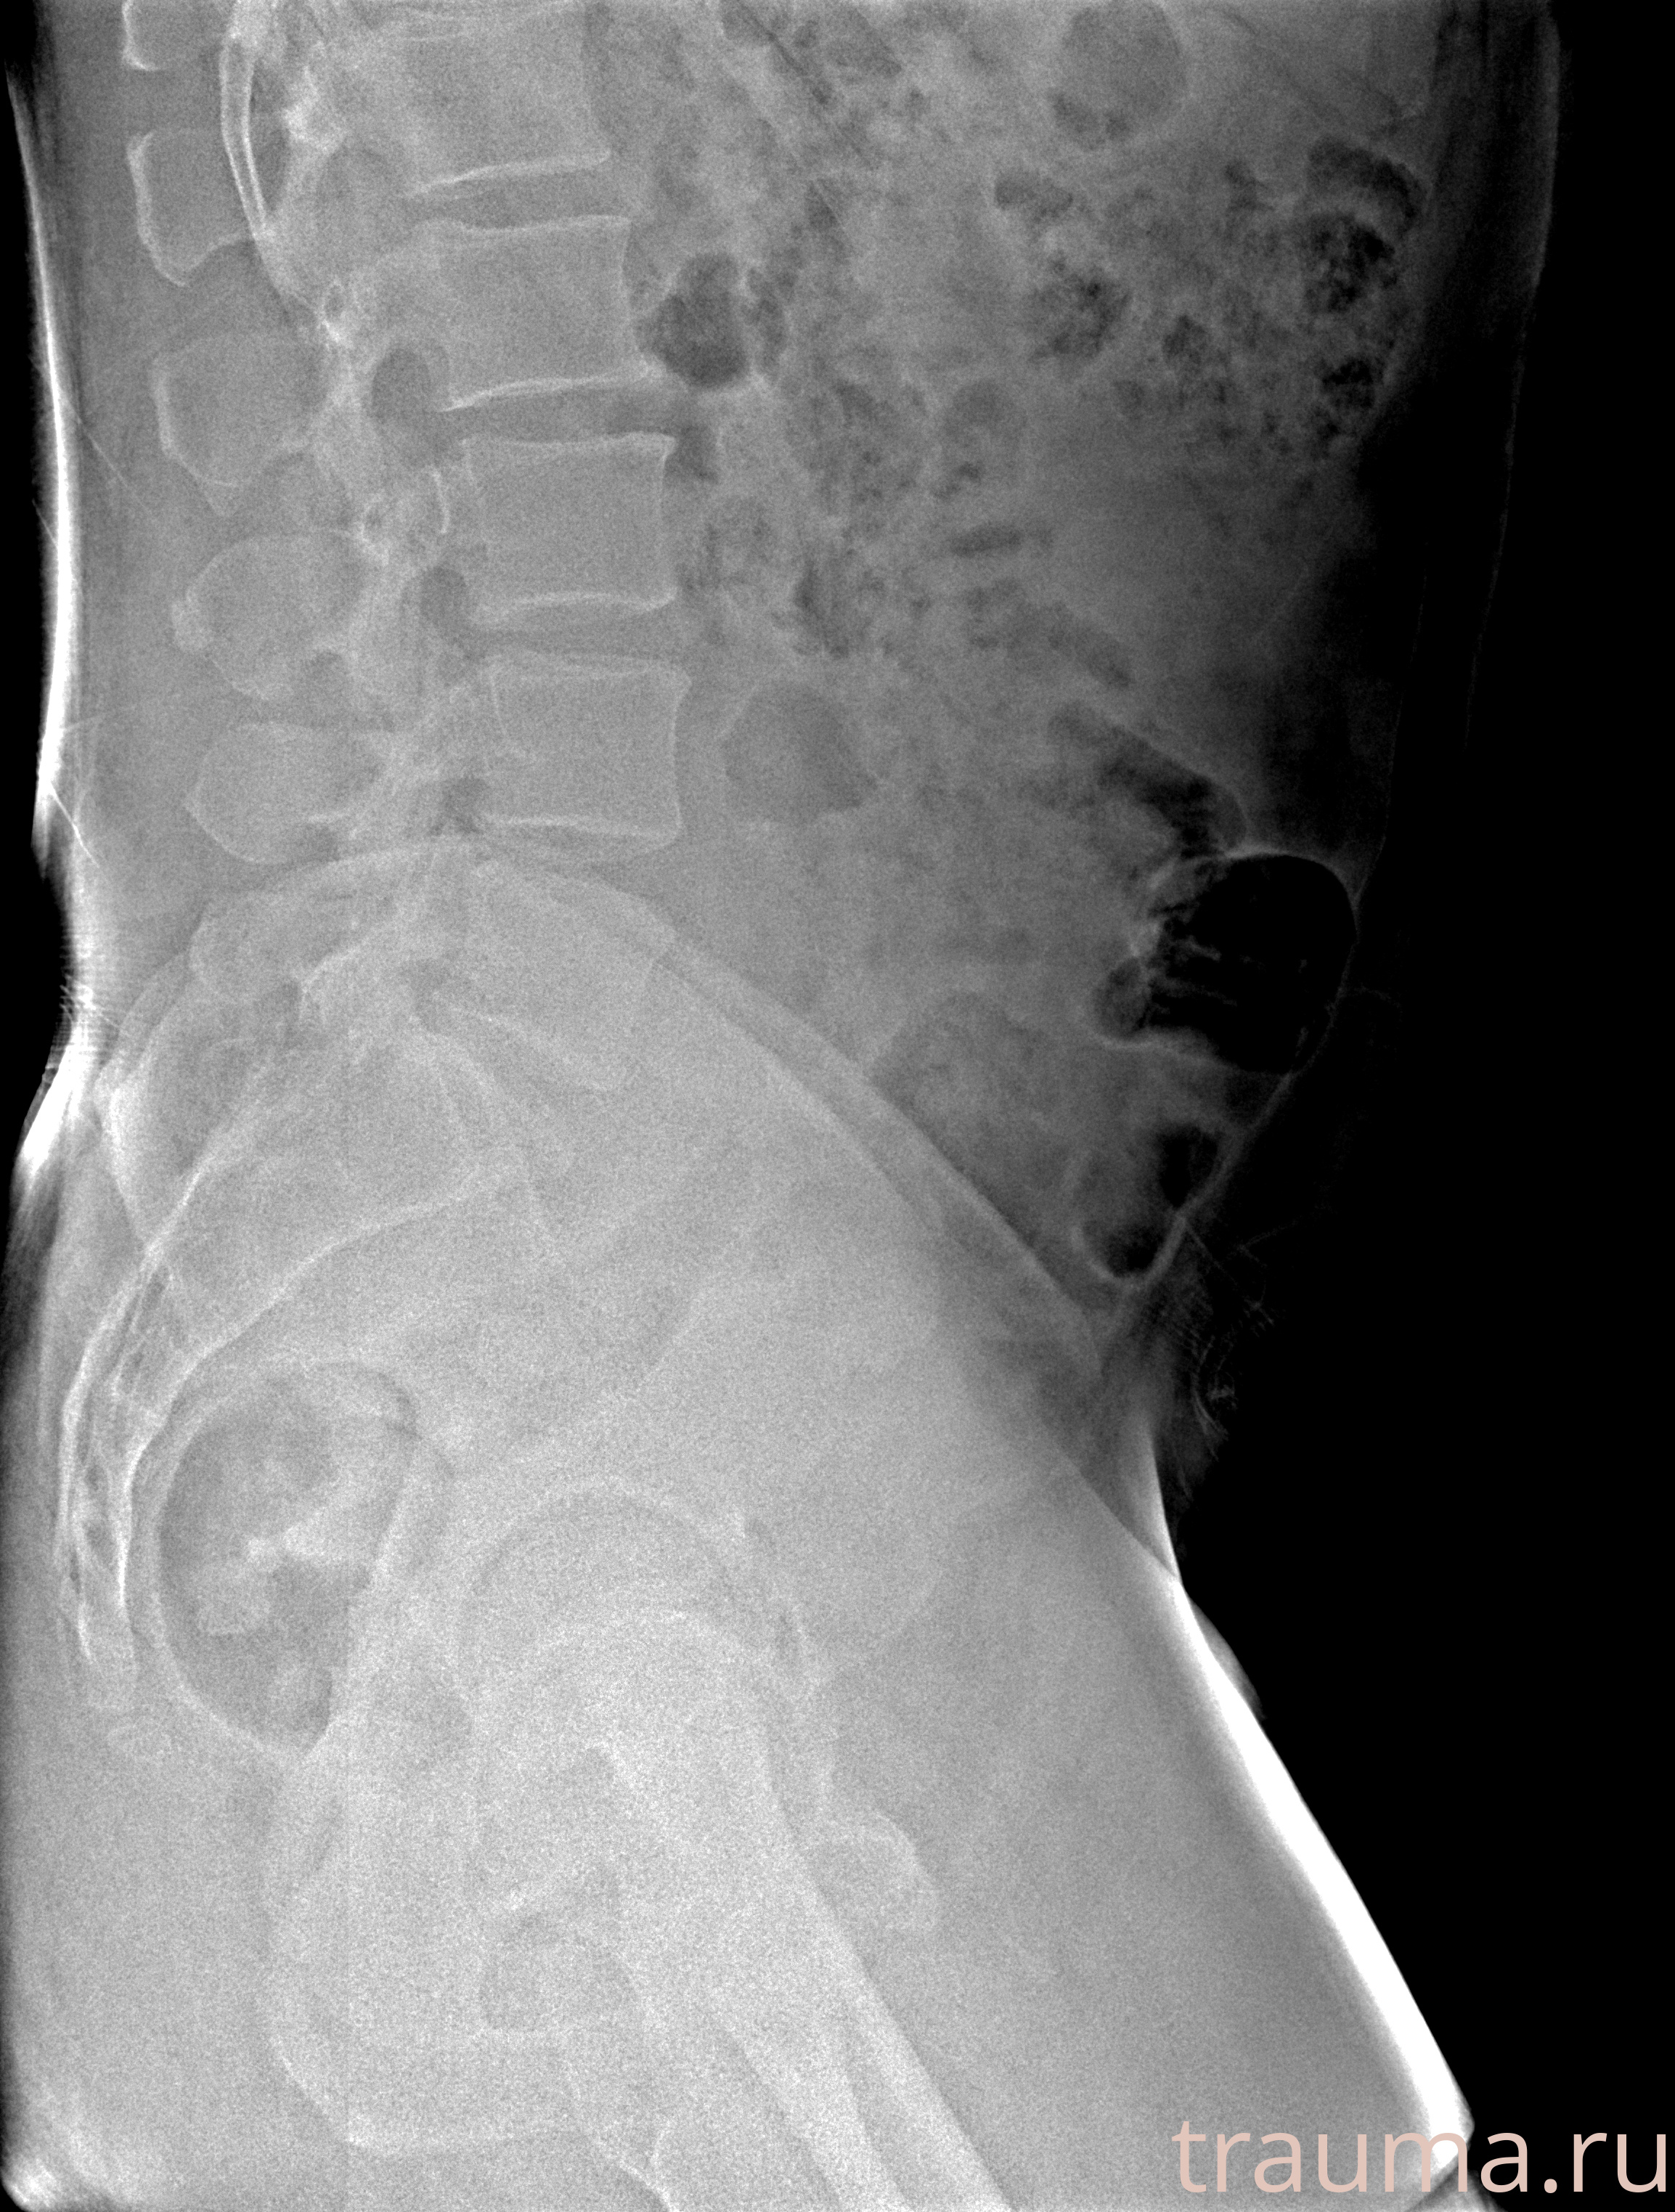

Рентгенограммы

Рентген на дому: по вашему адресу приезжает врач-рентгенолог, травматолог-ортопед с мобильным рентгеновским аппаратом, проводит диагностику травмы или заболевания, делает необходимые рентгенограммы, дает рекомендации по дальнейшему лечению. Получить качественные снимки в домашних условиях возможно благодаря уникальной методике, разработанной МосРентген Центром для института  Склифосовского